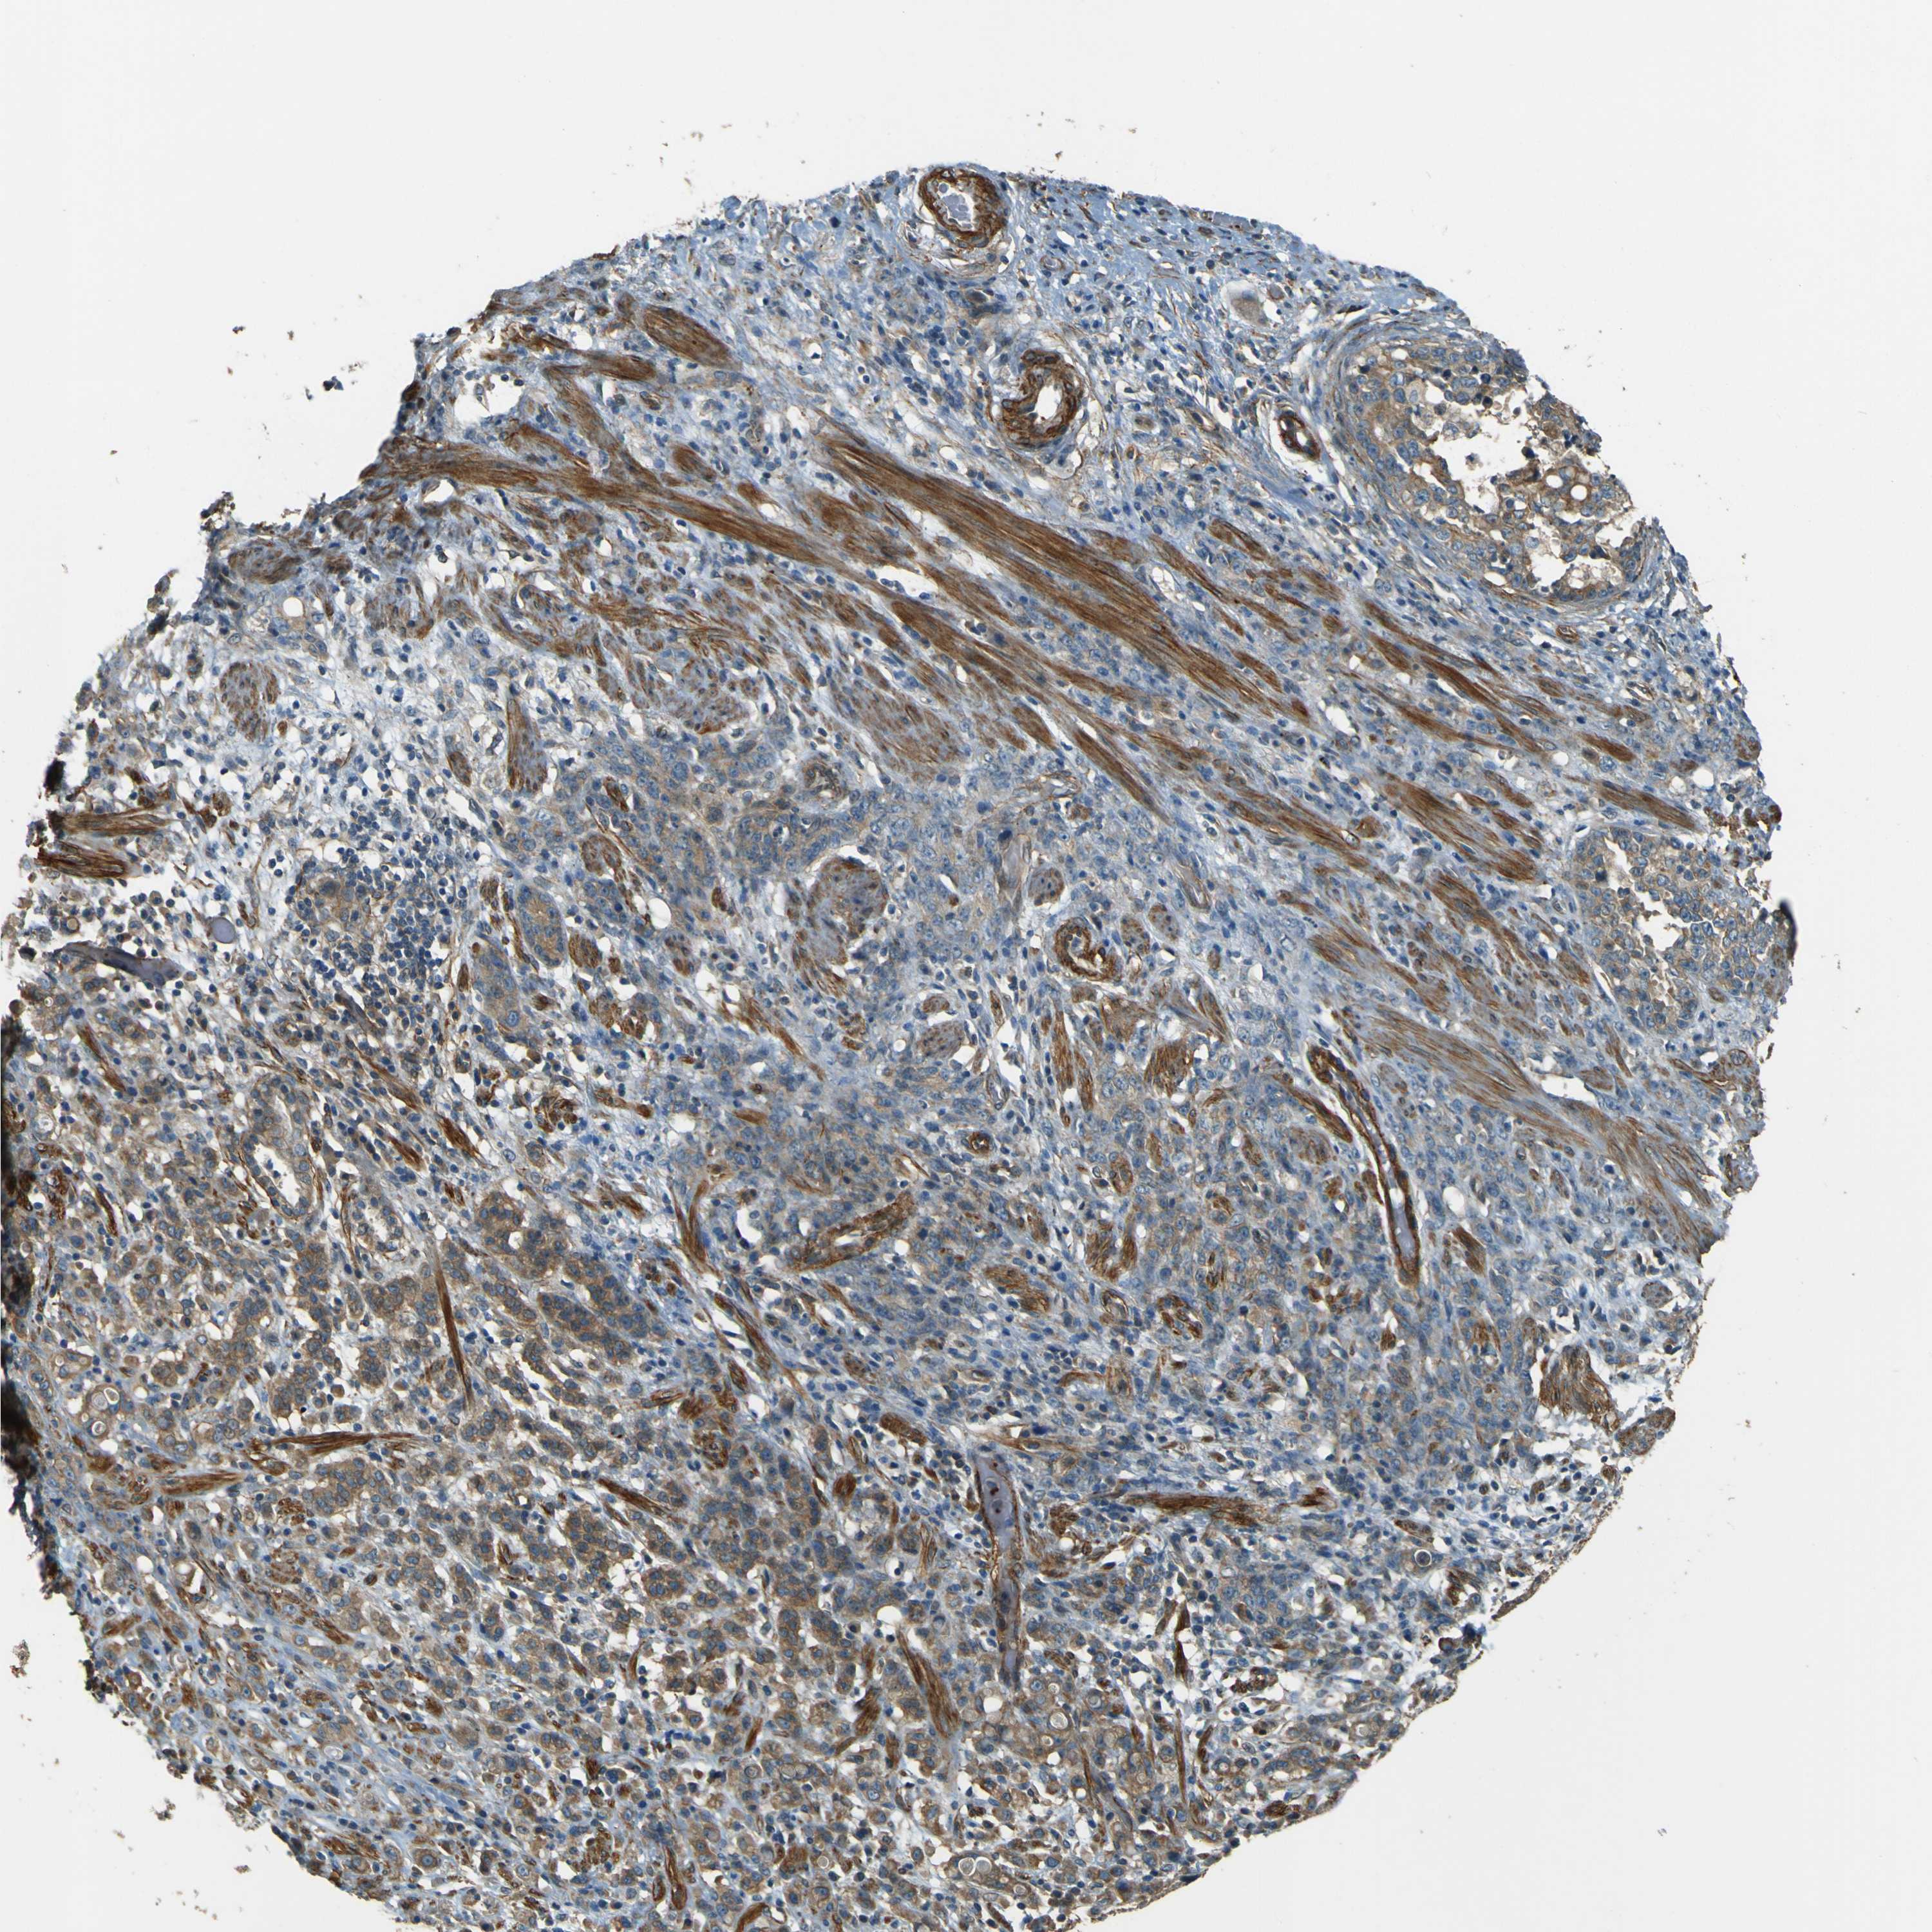

STOMACH CANCER - Protein expressioni

A mouse-over function shows sample information and annotation data. Click on an image to view it in a full screen mode. Samples can be filtered based on level of antibody staining by selecting one or several of the following categories: high, medium, low and not detected. The assay and annotation is described here.

Note that samples used for immunohistochemistry by the Human Protein Atlas do not correspond to samples in the TCGA dataset.

Antibody stainingi

Antibody staining in the annotated cell types in the current human tissue is reported as not detected, low, medium, or high, based on conventional immunohistochemistry profiling in selected tissues. This score is based on the combination of the staining intensity and fraction of stained cells.

Each image is clickable and will lead to virtual microscopy that enables deeper exploration of all samples and also displays staining intensity scores, fraction scores and subcellular localization as well as patient and tissue information for each sample.

Antibody HPA011185

Staining

High

Medium

Low

Not detected

Intensity

Strong

Moderate

Weak

Negative

Quantity

>75%

75%-25%

<25%

None

Location

Nuclear

Cytoplasmic/membranous

Cytoplasmic/membranous,nuclear

Adenocarcinoma, NOS

Adenocarcinoma, High grade